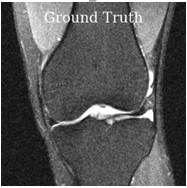

Deep learning based techniques achieve state-of-the-art results in a wide range of image reconstruction tasks like compressed sensing. These methods almost always have hyperparameters, such as the weight coefficients that balance the different terms in the optimized loss function. The typical approach is to train the model for a hyperparameter setting determined with some empirical or theoretical justification. Thus, at inference time, the model can only compute reconstructions corresponding to the pre-determined hyperparameter values. In this work, we present a hypernetwork based approach, called HyperRecon, to train reconstruction models that are agnostic to hyperparameter settings. At inference time, HyperRecon can efficiently produce diverse reconstructions, which would each correspond to different hyperparameter values. In this framework, the user is empowered to select the most useful output(s) based on their own judgement. We demonstrate our method in compressed sensing, super-resolution and denoising tasks, using two large-scale and publicly-available MRI datasets. Our code is available at https://github.com/alanqrwang/hyperrecon.